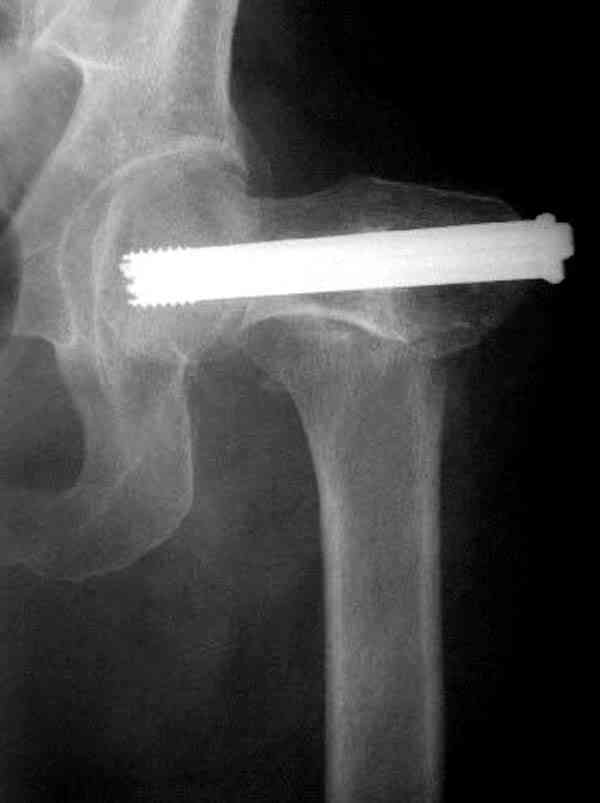

Коллега Челноков прав, здесь еще имеется риск перелома за счет ослабления латерального кортекса. Во время установки канюлированных шурупов за редким исключением спица вводится с одного раза, множественные попытки ослабляют латеральный кортекс, что станет источником перелома в этом месте.

В идеале для профилактики рефрактуры шурупы надо вводить не больше, чем под 130 градусным углом и не ниже уровня малого вертела.

Здесь случай перелома из-за ослабления латерального кортекса через 3 недели после операции на шейке. Шурупы были установлены под большим углом, слабый латеральный кортекс не выдержал нагрузку.